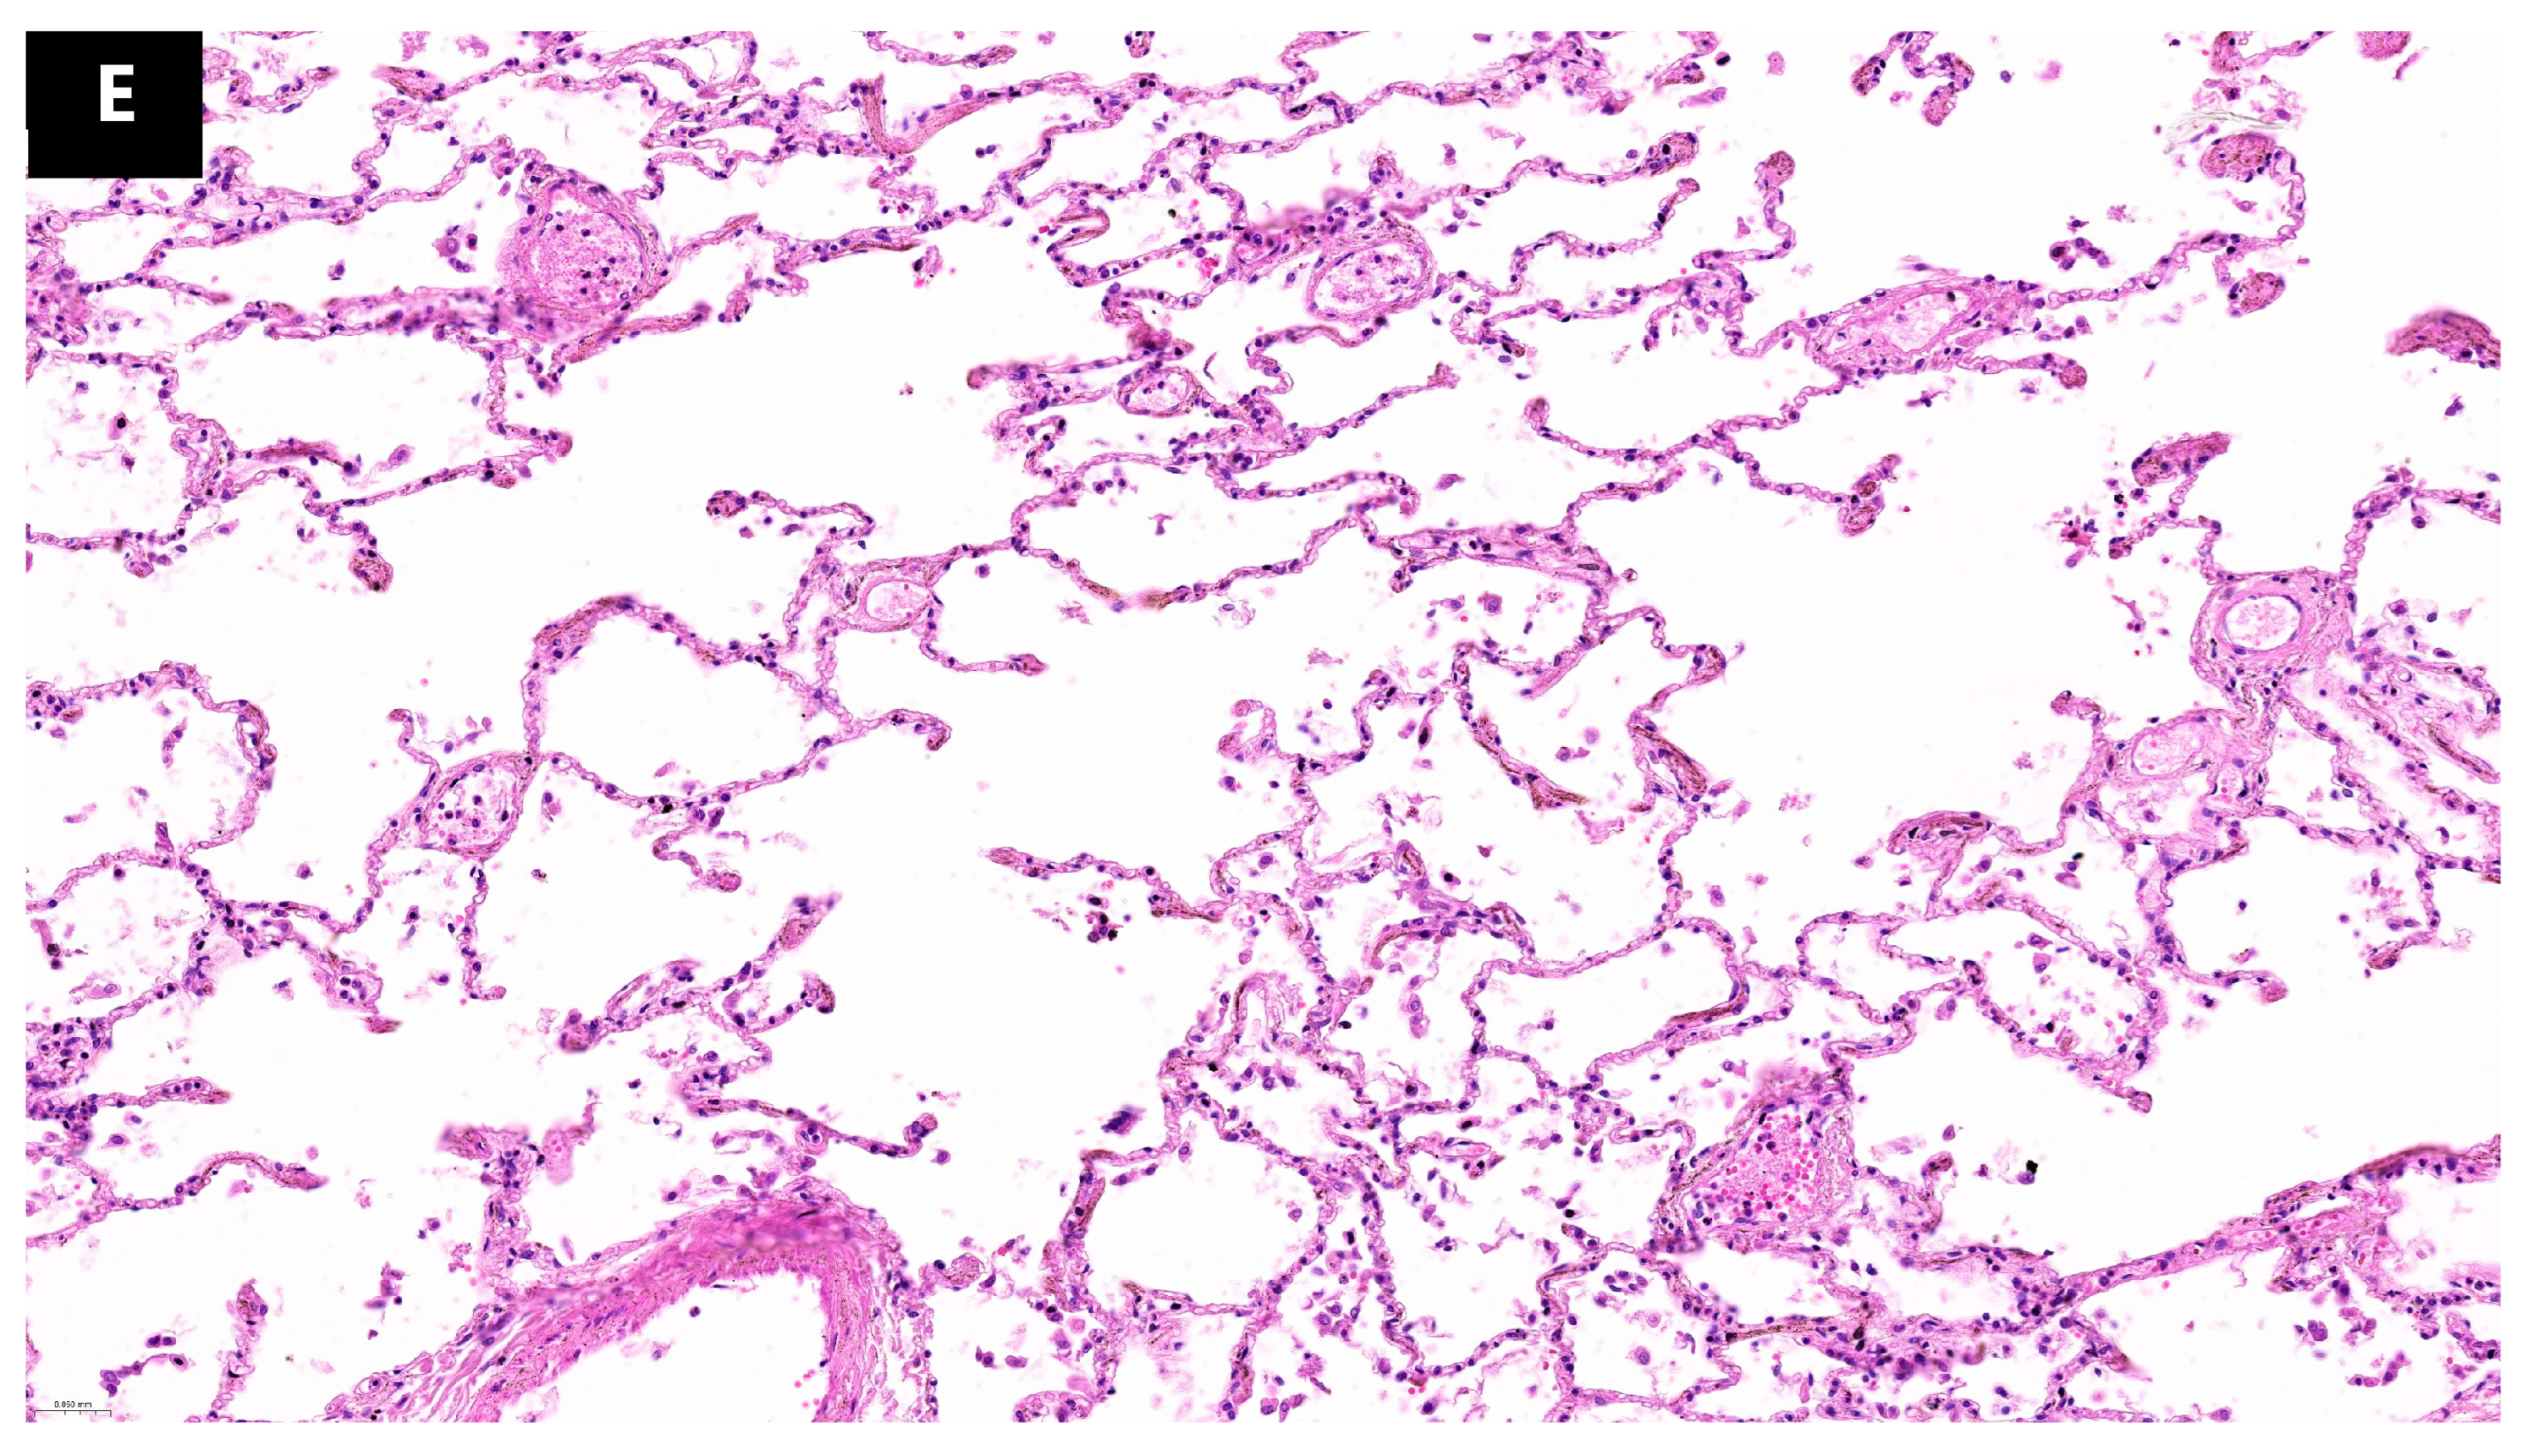

During histopathological examination, numerous microscopic lesions in the pulmonary tissue corresponding to alterations in remodeling and tissue regeneration processes were observed, likely indicative of a prolonged evolution of SARS-CoV-2 infection. These lesions, termed aberrant regenerative changes, encompassed organizing pneumonia, interstitial fibrosis, and alveolar squamous metaplasia (

Figure 3). Aberrant regenerative lesions succeeded the acute lesions of the exudative phase, including hyaline membranes, type II pneumocyte hyperplasia, alveolar hemorrhage, and inflammatory infiltrate, entering the spectrum of the proliferative organization phase within acute alveolar lesions [

18]. Thus, the study identified eight cases exhibiting at least one form of aberrant regenerative change. Among these, four cases presented organizing pneumonia, eight cases showed interstitial fibrosis, and five cases exhibited squamous metaplasia. Four cases presented all three forms described, one case presented two of the three forms, and three cases presented only one aberrant regenerative lesion. Correlating these findings with the time interval between the onset of symptoms and death, we observed that one out of three described lesions tend to emerge after a few days following infection (between 2 and 21 days) and after 23 days all three lesions described can be detected.

Among the aberrant regenerative lesions, the most frequent were extensive interstitial fibrosis (eight cases), followed by squamous metaplasia (five cases), and lastly, organizing pneumonia (four cases). The exact immunologic mechanism triggering pulmonary fibrotic processes in some patients is not fully understood, However, certain studies suggest that the major role in these processes is played by the exaggerated activation of monocyte-derived macrophages (CD163/LGMN-Mϕ) rather than tissue macrophages. The former interact extensively with fibroblasts and myofibroblasts, leading to the overstimulation of genes encoding extracellular matrix (ECM) [

43]. In line with the current study analysis, we noticed an association between interstitial fibrosis and the massive presence of alveolar macrophages. Parimon T. et al. also suggest that the fibrogenic mechanism is largely induced by the presence of long-lived circulating monocytes in the pulmonary parenchyma stimulated by numerous cytokines, frequently observed in patients diagnosed with cytokine storm [

44]. In the case of squamous metaplasia, we identify several signaling pathways activated in type II pneumocytes by secreted inflammatory factors, inducing the transformation of pneumocytic epithelium into squamous epithelium. These signaling pathways are much more expressed in SARS-CoV-2 infection when compared to other viral infections, such as influenza, demonstrating the increased specificity of this type of lesion in the context of COVID-19 pneumonia [

45].